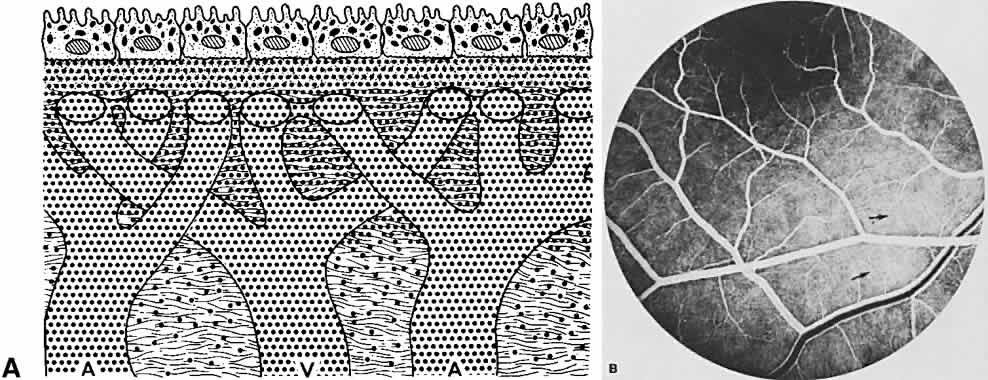

Within 3 to 5 minutes, the fluorescein is distributed equally throughout the blood. It is rapidly eliminated, predominantly by the kidneys14,16,22; most of it is removed from the bloodstream within 1 hour. Patients should be alerted to expected changes in skin tone and urine color in the post-test period. Oral administration of fluorescein is also possible in those individuals for whom intravenous injection is difficult or impossible. Oral administration allows assessment of the blood-retinal barrier, but it is inadequate in determining blood flow velocities or anatomic detail.23–25 Ten percent sodium fluorescein is mixed with orange juice to give a 1% to 2% solution; 1 g of dye is given to patients weighing 50 kg or less. More dye, up to a maximum of 2 g, is given to heavier patients.23 Serum concentrations of orally administered fluorescein peak at 30 minutes and remain relatively stable for 1 to 2 hours at levels similar to intravenously administered dye.23 Although the reported incidence of side effects is reduced with this route, allergic reactions still may occur.26 TOXICITY Although numerous reports of side effects secondary to fluorescein administration are present in the literature, it remains a remarkably safe diagnostic compound. Nausea and emesis are the most commonly reported reactions, occurring with a frequency of 5% or less.27 Syncope, thrombophlebitis, temperature elevation, nerve palsy, and local tissue necrosis are classified as moderate adverse reactions whose incidence is less than 1%.20,26,27 Severe adverse reactions requiring aggressive intervention include laryngeal edema, bronchospasm, anaphylaxis, circulatory shock, and myocardial infarction. A survey by Yannuzzi and associates reported one related death in more than 220,000 angiographic studies of the ocular fundus.27 With patients in whom toxicity is suspected, an intradermal skin test has been recommended.25 An emergency tray and oxygen should be available whenever fluorescein is administered. Prophylaxis for possible adverse reactions is controversial. Although there have been no reports of human fetal complications secondary to fluorescein injection during pregnancy, many physicians avoid administration if possible in pregnant individuals.27,28 ANATOMIC CONSIDERATIONS Fluorescein angiography of the iris and fundus is possible because of the unique specialization of the eye as an optical instrument. Only in the eye is the vascular system open to close scrutiny through noninvasive means. The ocular fundus has two distinctly separate vascular systems—retinal and choroidal—separated by a specialized pigmented monolayer, the retinal pigment epithelium (RPE). Embryologically, the sensory retina and RPE are derived from the inner and outer layers of the optic cup. The choroid and its vasculature lie posterior to the RPE. The fluorescein angiographic patterns of the posterior uvea are, therefore, always partially obscured by the RPE (Fig. 4). The degree of pigmentation and the pathologic changes in this pigmented layer markedly influence the choroidal angiographic appearance. In the interpretation of fundus fluorescein angiograms, the physician must keep in mind and be familiar with the anatomy and interaction of these three layers. CHOROID The choroid is a highly vascular connective tissue layer with an average width of 0.25 mm. It is made up of three distinct layers and is perfused by the long posterior, short posterior, and recurrent anterior ciliary arteries. Drainage is primarily through the vortex veins. Its capillary system, the choriocapillaris, is innermost and lies directly beneath Bruch's membrane. The choriocapillaris has a lobular pattern made up of a central arteriole, peripheral draining venules, and an intervening capillary bed. The capillary walls are extremely thin and contain multiple fenestrations, allowing a high degree of fluid transport (Fig. 5). These fenestrations are thought to be actual openings in the endothelial wall through which fluid can undergo passive exchange between the lumen of the vessel and the surrounding extravascular space. As fluorescein enters the choriocapillaris, it quickly passes into the extracellular space. The outer choroidal layers are nonfenestrated and, similar to other typical arteries and veins, do not normally leak fluorescein dye. Under normal conditions, the choroid begins to fill with fluorescein a moment prior to the retinal vascular system. This filling is difficult to study by fluorescein angiography because of obscuration by the overlying retina and RPE, its rapid filling, and leakage of fluorescein from the choriocapillaris.6 RETINAL PIGMENT EPITHELIUM The RPE is a specialized monolayer of pigmented epithelial cells separating the choroid and sensory retina. It functions physiologically as both a metabolic support platform for the overlying photoreceptors and as an effective barrier against passive molecular transport between the choroid and retina.29,30 In its normal state, the RPE prevents leakage or transport of fluorescein into or out of the choroidal space. The RPE also functions as an optical barrier because of the presence of pigmented melanosomes (Fig. 6). The density of this pigment varies with retinal location; it is greatest in the foveomacular region and least anterior to the equator. There are more pigmented epithelial cells per unit area in the foveomacular region than in the periphery. Posteriorly, the cells are tall and columnar, with several layers of melanosomes crowded together. Anteriorly, the cells gradually become flatter and more cuboidal, with a corresponding loss of relative pigment concentration (Fig. 7). In any normal eye, regardless of the comparative fundus color, the greater pigmentation in the foveomacular area gives this zone a darker clinical appearance when compared with the remainder of the posterior pole and periphery. RETINA The retina, except for its vasculature, may be regarded as a transparent tissue comprised of tightly packed layers of cells with essentially no extracellular space. The retina is perfused by the central retinal artery and cilioretinal vessels present in 32% of eyes.31 The capillary bed is nonfenestrated and fluorescein does not, therefore, leak from the retinal vessels into the surrounding tissue (Fig. 8). Functionally, the retinal vasculature represents a “closed” system, as opposed to the choroid, in which fluorescein is free to move between the intravascular and extravascular compartments. The retinal circulation normally fills with fluorescein after the choroidal flush; however, a cilioretinal artery fills at the same time as the choroid, preceding the rest of the retinal circulation. The retina also serves as an optical filter because of its high content of xanthophyll pigment, especially in the macular region. This yellow pigment has its highest concentration in the outer nuclear and plexiform layers, and may selectively absorb blue excitation frequencies.16 IRIS The iris stroma, like the choroid, is composed of vascular connective tissue. Although electron microscopy and tracer studies have demonstrated the absence of fenestrations in both animal and human eyes,32–34 other reports have supported the presence of gaps in the junctions between endothelial cells in some animal iris tissue.34–36 |

Fluorescein is removed from the choroid in the reverse manner. As vascular fluorescence becomes less because of recirculation of dye and removal by the kidneys, the extravascular fluorescein passes back into the vessels and is eliminated. Once the choroidal fluorescence has become more concentrated in the extravascular compartment, the relative contrast to vascular fluorescence remains throughout the entire study. Fluorescein most likely leaves the extravascular tissue in the area of the choriocapillaris first and the outer choroid and inner scleral layers last. This dilution causes the extravascular fluorescein of the inner choroidal layers to become less concentrated than the outer extravascular choroidal fluorescein (Fig. 16). This is seen when the large choroidal vessels stand out in dark relief against the more concentrated extravascular fluorescence of the outer choroidal layers (see Fig. 16B). Even in the late phase, when fluorescein is no longer seen in the vasculature, patterns of choroidal fluorescence arising from extravascular fluorescein can be seen. This very late extravascular fluorescence arises from the outer choroidal and inner scleral layers (Fig. 17). The RPE, with its tight junctions, acts as a barrier to the leakage of fluorescein from the choroid into the overlying outer retinal layers. Within 1 second of the choroidal flush, fluorescein dye is seen within the arterioles. In a healthy patient, with proper administration of fluorescein, this occurs rapidly, filling the arterioles completely. As bloodborne dye crosses the capillary network and enters the venous system, a columnar appearance to the veins initially is observed—the laminar venous phase. It occurs secondary to margination of fluorescein because of more rapid flow of blood in the vein's central lumen.16 As more fluorescein enters the veins, they (fill totally—full venous phase. Arteriovenous transit is dependent on the distance fluorescein dye must flow and is therefore delayed in the fundus periphery and more rapid within the macula. |

secondary to an overlying pathologic condition. HYPERFLUORESCENCE Hyperfluorescence due to accumulation of fluorescein in an area where it is not normally seen is well portrayed in a focal detachment of the RPE (Fig. 18), in which the dye accumulates between the RPE and Bruch's membrane (see Fig. 18A). The RPE appears to be firmly attached to Bruch's membrane, and when fluid accumulates in this area, the RPE delineates itself with sharp, abrupt borders (see Fig. 18B-D). Central serous chorioretinopathy causes an area of hyperfluorescence because of the presence of the dye between the retinal photoreceptor cells and the RPE (Fig. 19). This may be related to a detachment of the RPE and is associated in some way to a defect in the normal mechanism of fluid exchange across the RPE between the choroid and the sensory retina. The attachment of the photoreceptors to the RPE may not be as strong as the attachment of the RPE to Bruch's membrane. This may be why the borders of fluorescence in the secondary serous retinal detachments found in central serous chorioretinopathy are more diffuse (see Fig. 19B) than those in a detachment of the RPE (see Fig. 18B). Ocular histoplasmosis may also show choroidal hyperfluorescence because of the abnormal presence of a choroidal neovascular membrane forming a nodular elevation of the RPE (Fig. 20A and B). In the early stage of this disorder, when a neovascular tuft is clearly seen, the very early phases of the fluorescein study clearly show the new vessels filling with fluorescein. In the later phases, dye leaks from the vessels to fill the surrounding tissue and may even cause staining of the RPE (see Fig. 20C-E). Hyperfluorescence is also caused by an increased concentration of fluorescein in an area of the uveal tract, where it is normally seen in the intravascular and extravascular components of the choroidal stroma. A choroidal hemangioma shows hyperfluorescence very early in the study (Fig. 21A and C). This vascular tumor and the choroidal vasculature fill with dye at the same time. For this reason, these lesions often reach a peak of hyperfluorescence in the early phases of the fluorescein study. Even though there is leakage and staining of the extravascular components, because these are highly vascular tumors, the peak of the hyperfluorescence may diminish before the late phases of the study (see Fig. 21D and E). Hyperfluorescence from a solid tumor (e.g., a choroidal melanoma or metastatic lesion; Figs. 22 and 23) also is caused by an increased accumulation of fluorescein in the uveal stroma at the tumor site. These masses are usually associated with increased vascularity and therefore increased fluorescence. Fluorescein leaks rapidly into the extravascular space to fill the stroma of these tumors (see Figs. 22A and 23A). Because these are solid tumors of densely packed cells, it probably takes time for the fluorescein to completely penetrate the extravascular space of the tumor. Lesions of this nature may show a delay in the hyperfluorescent peaks as compared with choroidal hemangiomas, and for the same reason may fluoresce longer. Hyperfluorescence, as seen with the previously mentioned tumors, also results from transmission through pigment epithelial defects and from the presence of fluorescein in cystic spaces within the retina. Hyperfluorescence may also be caused by the transmission of normal background choroidal fluorescence through defects of the RPE secondary to various pathologic conditions. In albinism, a defect in production of melanosomes leads to increased transmission of choroidal fluorescence through the nonpigmented RPE (see Fig. 17). With degenerative disease affecting the RPE, focal areas lacking pigment are seen with adjacent areas of hyperpigmentation. In the early phases of a fluorescein study, the choroidal fluorescence is transmitted through these defects in the RPE,43 whereas in the late phases, there is actual staining with fluorescein in these areas (Fig. 24). The adjacent focal areas of hyperpigmentation cause blockage of the background choroidal fluorescence. Drusen may act in the same manner because the RPE may be thinned over these lesions.44 Transmission of the choroidal fluorescence occurs early, whereas actual staining with the dye is seen late (Fig. 25). HYPOFLUORESCENCE Hypofluorescence from absence of fluorescein in an area where it would normally be seen may be secondary to a lack of perfusion or to absence of the tissue. The hypofluorescence seen in the early frames of an individual with a coloboma results from the absence of the choriocapillaris; even though the RPE is absent, there is only transmission of the large choroidal fluorescein-filled vessels (Fig. 26A and B). In the very late stages of the study, the coloboma hyperfluoresces secondary to scleral staining in the area devoid of RPE (see Fig. 26C and D). Hypofluorescence can also be secondary to a relative decrease in the fluorescein concentration. This may partially explain why a choroidal nevus does not fluoresce (Fig. 27). In addition to the nevus cells occupying space where the dye would normally accumulate, hypofluorescence is also caused by obscuration of fluorescence by the heavy concentration of pigment (Fig. 28). (Obscuration or blockage of choroidal fluorescence as a mechanism of hypofluorescence may be seen in several other conditions. A hemorrhage under the RPE causes a corresponding area of hypofluorescence due to a blockage of the underlying fluorescence (Fig. 29). For the same reason, an area of hypertrophy of the RPE will appear hypofluorescent (see Fig. 28). In addition, patients with Stargardt's disease often exhibit a silent choroid secondary to blockage of background choroidal fluorescence by lipofuscin accumulation in the RPE (Fig. 30).

In patients with choroidal folds, there are alternating areas of hypofluorescence and hyperfluorescence (Fig. 31).45 The hypofluorescent lines correspond to the areas between the peaks of the folds where the RPE pigment concentration is greatest, causing a relative blockage of the underlying fluorescence. The alternating hyperfluorescent lines represent the peaks of the folds where the pigment concentration is less, allowing a greater transmission of the choroidal fluorescence. |